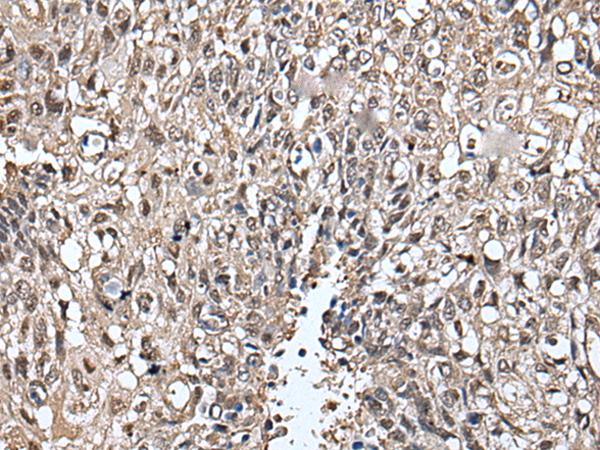

IHC positive control: |

Human lung cancer and human prostate cancer |

IHC Recommend dilution: |

25-100 |